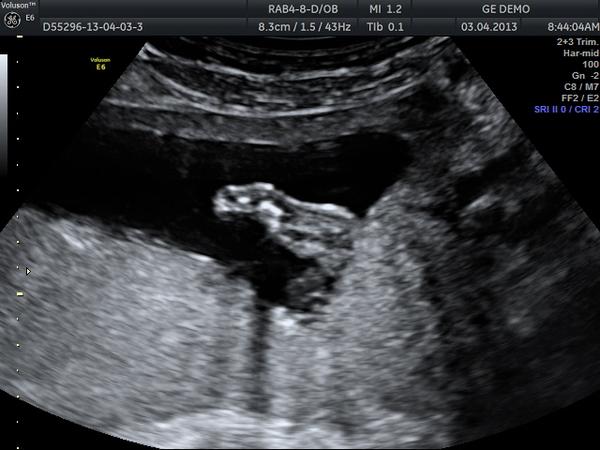

dámy dámy už to viem moje tušenie bolo správne k mojmu chlapčekovi pribudne krasna malá sestrička :*